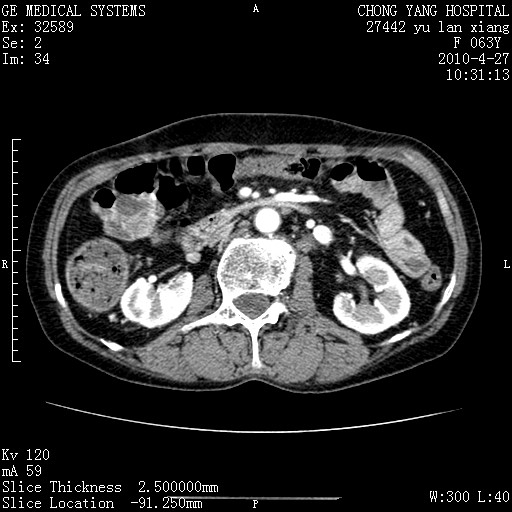

标题: CT26066:F63Y 上腹正中压痛半月,CA199:7400u/ml,MR示胰腺炎伴 [打印本页]

胰腺癌侵犯腹腔动脉干-分支、胃壁、左侧膈肌伴胰周及腹膜后淋巴结转移、胆囊切除术后。

胰腺癌侵犯腹腔动脉干-分支、胃壁、左侧膈肌伴胰周及腹膜后淋巴结转移、胆囊未显影。